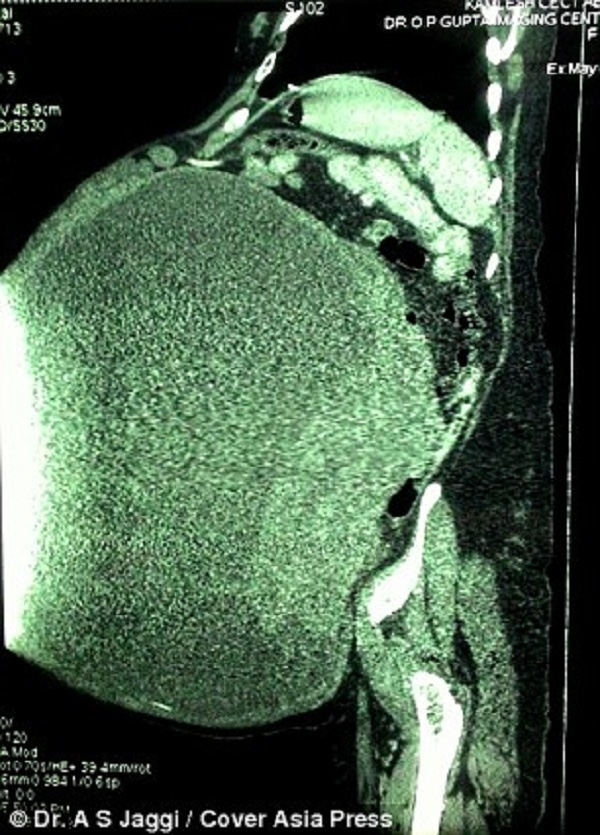

Sau 15 năm ròng chịu đựng đau đớn, Devi Kamlesh (Ấn Độ) mới thoát khỏi khối u nặng gần 1 tạ trong bụng mình. Khi mới phát hiện ra, vì gia đình không có điều kiện nên Devi Kamlesh phải chịu đựng cho đến khi người chồng qua đời mới dám đến bệnh viện khám.

Devi Kamlesh, một góa phụ sinh sống tại huyện Meerut, bang Uttar Pradesh, miền bắc Ấn Độ vừa trải qua một cuộc phẫu thuật để cắt bỏ khối u nặng gần 100 kg trong bụng mình sau 15 năm ròng chịu đựng đau đớn.

Vì gia đình không có đủ điều kiện chữa trị, chồng cô đã không cho cô đến bệnh viện. Dù hàng ngày bị cơn đau hành hạ, cô vẫn cố gắng chịu đựng theo lời chồng. Nhưng sau khi người chồng vừa qua đời cách đây 6 tháng, cô quyết định tìm gặp bác sĩ bởi khối u quá lớn, có trọng lượng bằng một con voi sơ sinh.

Bác sĩ A.S.Jaggi làm việc tại bệnh viện Lokpriya, Meerut đã đồng ý phẫu thuật cho Kamlesh hoàn toàn miễn phí để góp phần giúp đỡ những người nghèo không có điều kiện chữa bệnh. Ca mổ kéo dài ba tiếng đồng hồ và cuối cùng khối u đã được gỡ khỏi buồng trứng bên phải của cô.

Các bác sĩ vô cùng kinh ngạc trước kích thước khổng lồ của khối u. Nó có trọng lượng lên tới 97 kg, gấp 28 lần trọng lượng trung bình của một em bé sơ sinh. Bác sĩ Jaggi cho biết: “Khi tới bệnh viện, cô ấy vô cùng đau đớn. Khối u đã bắt đầu nứt vỡ. Nếu chậm trễ thêm bất cứ giờ nào, cô ấy có thể sẽ chết. Cô ấy cần truyền rất nhiều máu trong quá trình phẫu thuật và phải chăm sóc đặc biệt trong một ngày. Hiện tại bệnh nhân đang trong trạng thái hồi phục tốt”.

Bác sĩ Jaggi cũng chia sẻ, trong suốt 25 năm trong nghề, ông chưa từng nhìn thấy một khối u kinh khủng như vậy. Các khối u buồng trứng thông thường không có kích cỡ lớn như thế này. Nó dài gần 1 mét và rộng hơn 60 cm. Bệnh viện của ông đã liên hệ với ban tổ chức sách kỷ lục Limca Ấn Độ để ghi danh khối u này.